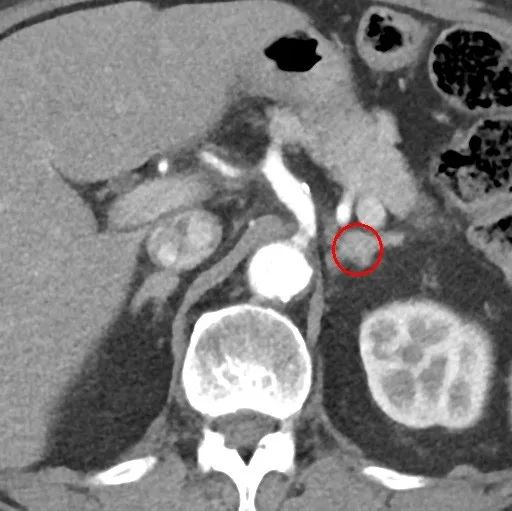

术前肾上腺增强CT检查:左侧肾上腺腺瘤。

图2. 红色圆圈指示左侧肾上腺腺瘤。